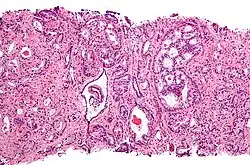

Gleason score 6 (3+3)

Cribriform pattern: Gleason grade 4

Gleason score 7 (3+4) with minor component of cribriform glands

Gleason 3

Gleason 3 is a clearly infiltrative neoplasm, with extension into adjacent healthy prostate tissue. The glands alternate in size and shape, and are often long/angular. They are usually small/micro-glandular in comparison to Gleason 1 or 2 grades. However, some may be medium to large in size. The small glands of Gleason 3, in comparison to the small and poorly defined glands of pattern 4, are distinct glandular units. Mentally you could draw a circle around each of the glandular units in Gleason 3.[4][7]

Gleason 4

Gleason pattern 4 glands are no longer single/separated glands like those seen in patterns 1–3. They look fused together, difficult to distinguish, with rare lumen formation vs Gleason 1–3 which usually all have open lumens (spaces) within the glands, or can be cribriform-(resembling the cribriform plate/similar to a sieve: an item with many perforations). Fused glands are chains, nests, or groups of glands that are no longer entirely separated by stroma-(connective tissue that normally separates individual glands in this case). Fused glands contain occasional stroma giving the appearance of "partial" separation of the glands. Due to this partial separation, fused glands sometimes have a scalloped (think looking at a slice of bread with bite taken out of it) appearance at their edges.[4][7]